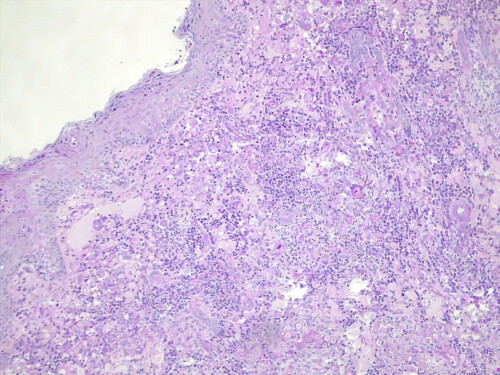

Cette dernière est négative mais l’analyse histopathologique, examinée en coloration standard et APS, montre des lésions nodulaires, isolées ou parfois coalescentes siégeant dans le derme et s’étendant jusque dans l’hypoderme, formées d’une plage dense de cellules macrophagiques dont le cytoplasme apparaît granuleux, basophile. Ces foyers granulomateux sont centrés par plusieurs éléments basophiles constitués d’un cément bleuté, parsemé d’éléments fongiques, ovoïdes, mais également filamenteux, réfringents. Aucun élément fongique n’est mis en évidence au sein des annexes cutanées, mais certains granulomes sont en rapport ou à proximité directe de follicules pileux (photos 5 et 6).

Photos 5 et 6 : aspect histopathologique des lésions : notez la présence de lésions nodulaires, isolées ou parfois coalescentes siégeant dans le derme et s’étendant jusque dans l’hypoderme (photo 5) et de foyers granulomateux centrés par des éléments fongiques, ovoïdes et filamenteux ramifiés (hyphes) (photo 6).